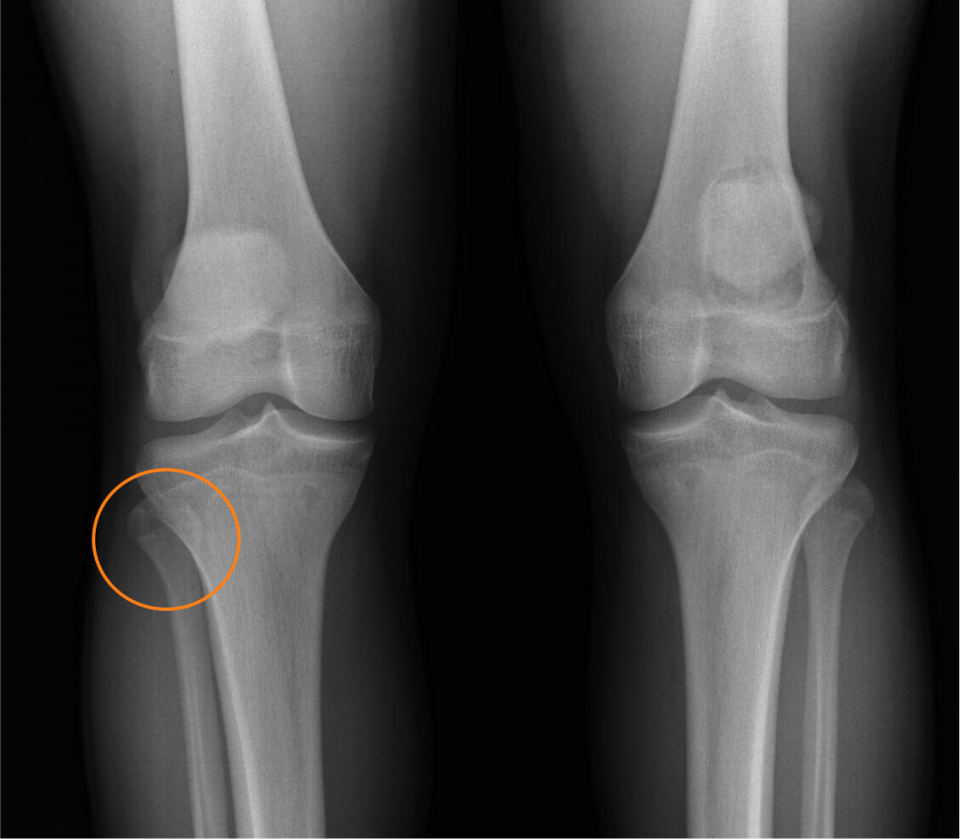

1番悪そうに見えても、そうとは限らない

1番悪そうに見えても、そうとは限らない